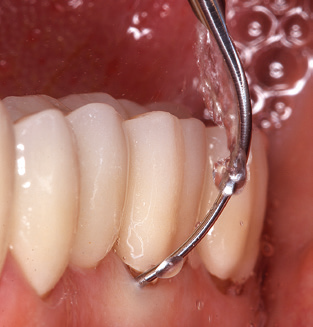

Die gute Ausleuchtung des Arbeitsfeldes stellt eine wesentliche Erleichterung dar. Bei dem von den Autoren genutzten System ist dies gelungen, indem ein 5facher LEDRing in das Handstück integriert wurde. Natürlich werden für dieses System unterschiedliche Arbeitsspitzen für die jeweiligen Indikationsbereiche angeboten. Eine gerade, universell einsetzbare Spitze ist das Basisinstrument zur maschinellen Instrumentierung natürlicher Zähne (Abb. 5a und b). Für schwer zugängliche Bereiche im Seitenzahnbereich werden gebogene Spitzen angeboten, die auch einen Zugang zu freiliegenden Furkationen ermöglichen (Abb. 6).